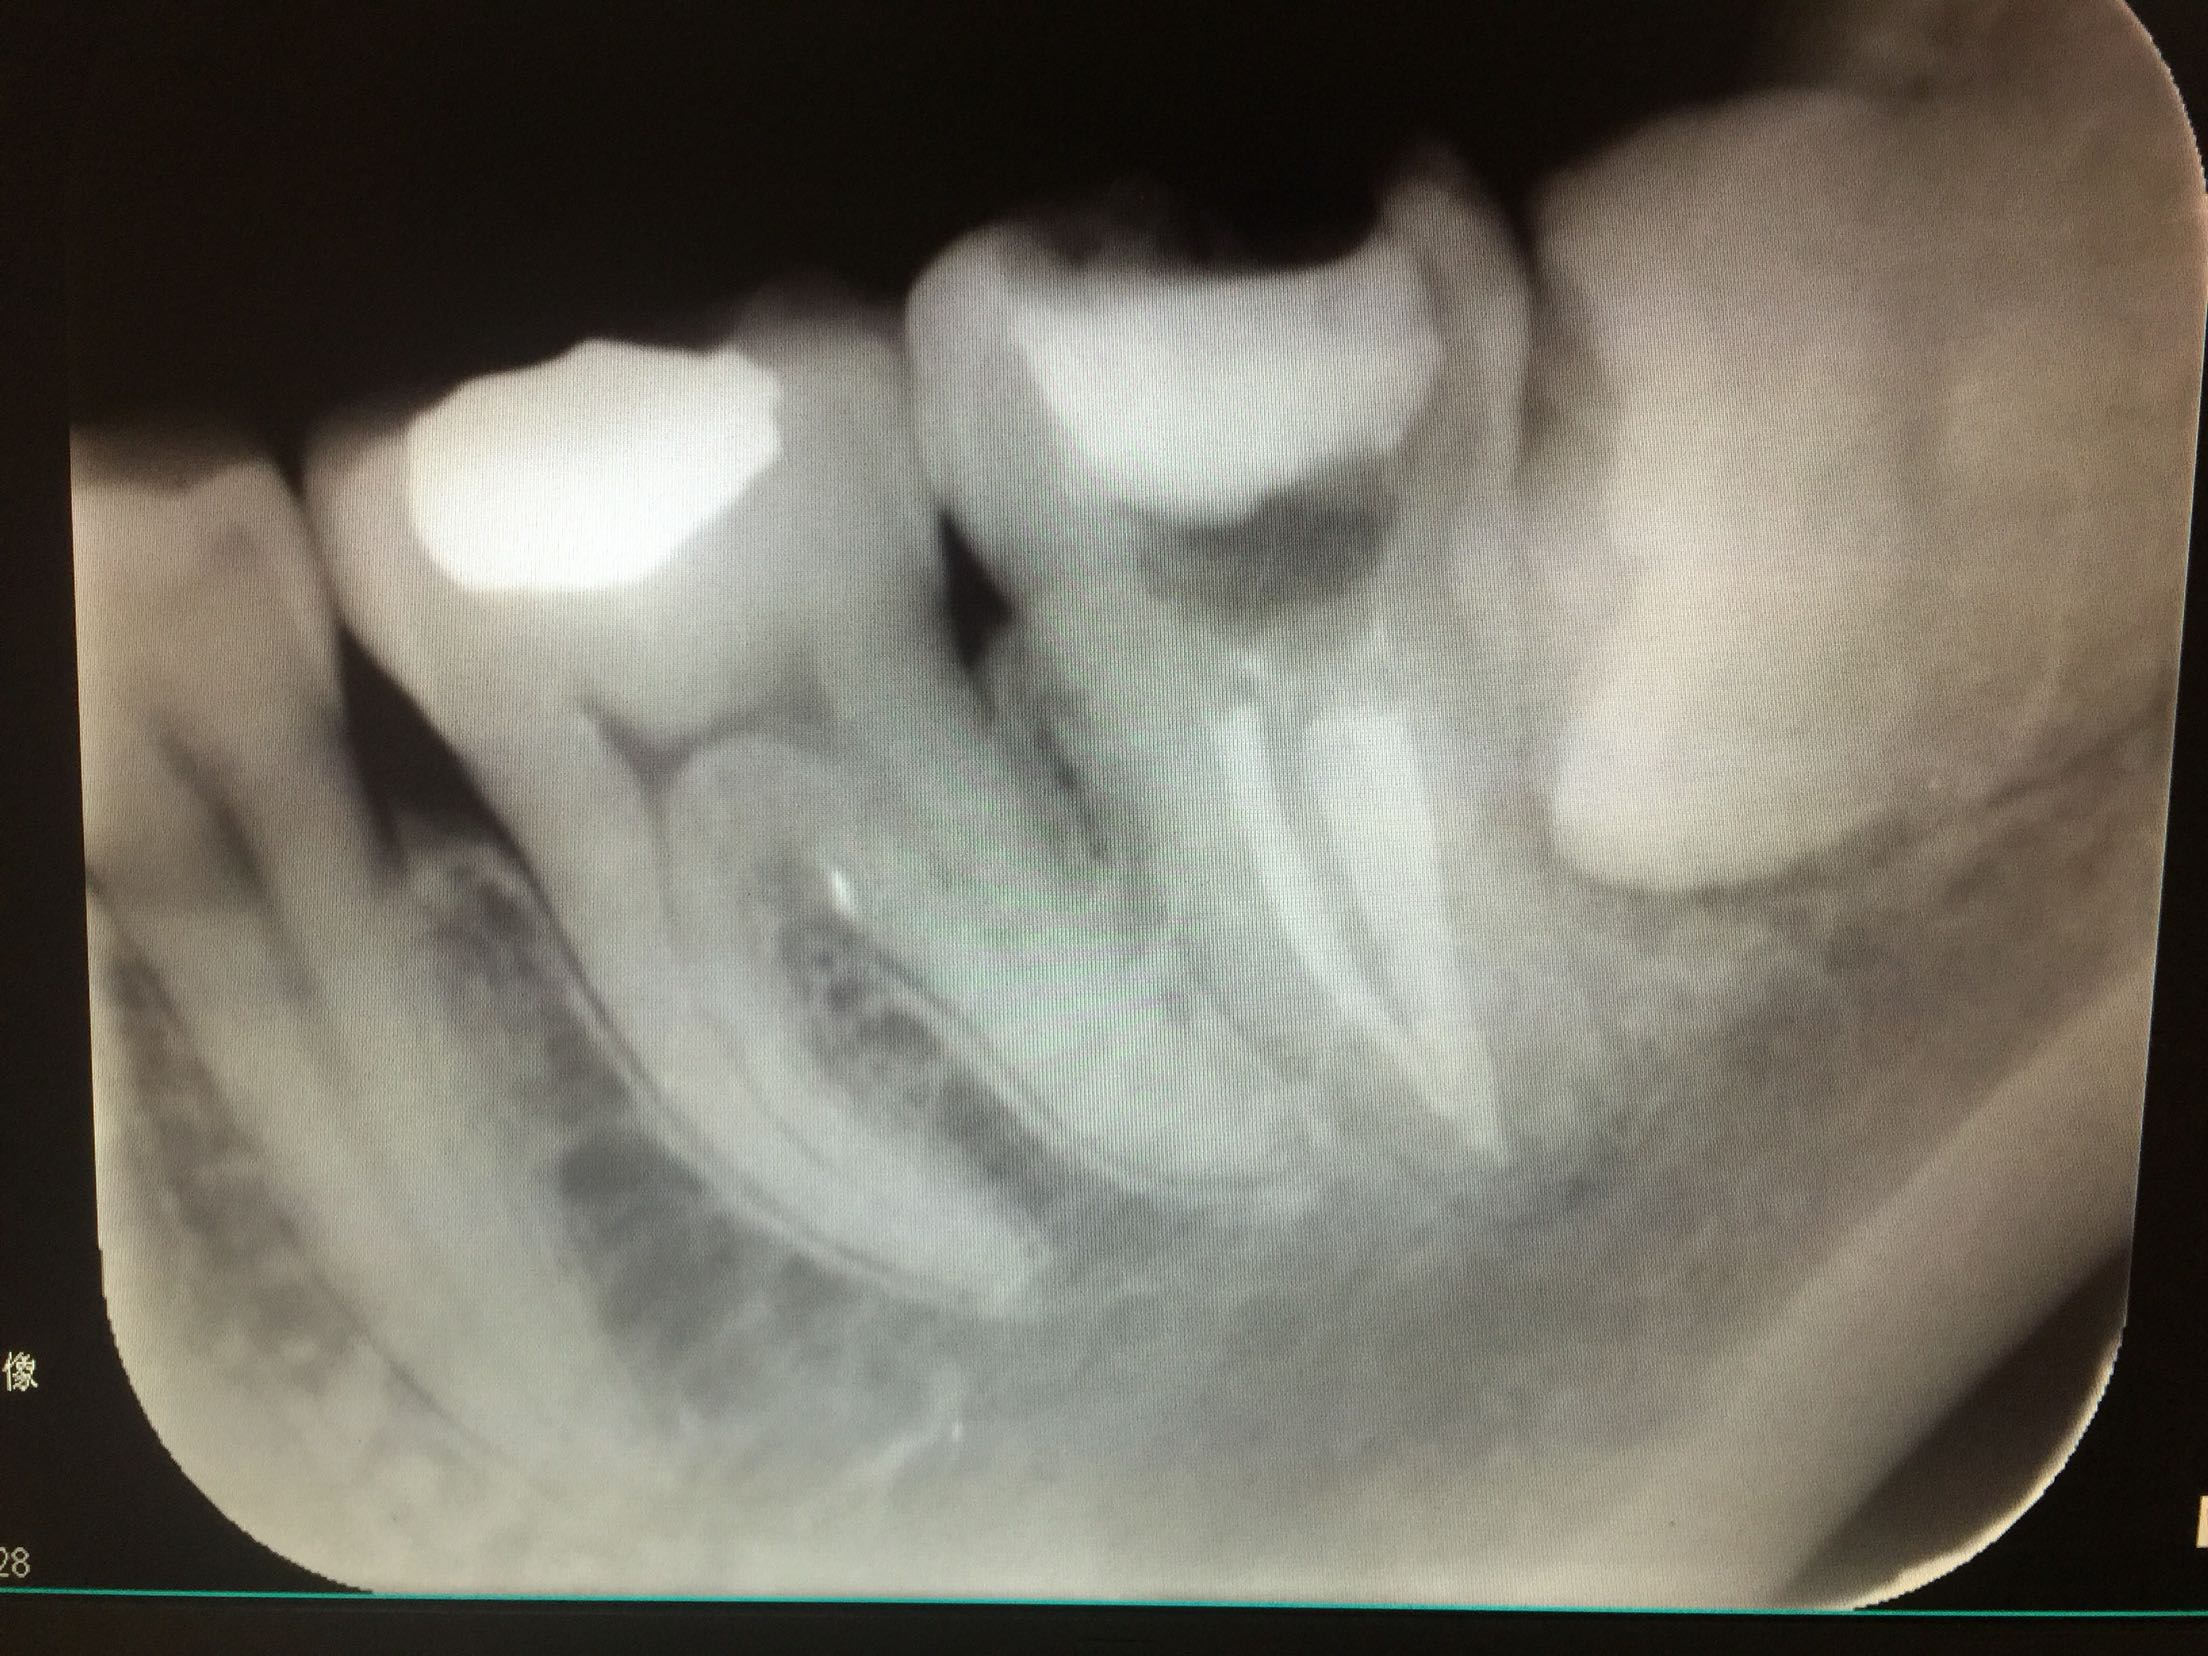

检查:37牙合面可见树脂补料,有继发龋,边缘不密合。冷+,探+-,叩-,不松。18.28.38.48近中阻生,无龋坏。 X线示:37牙合面可见高密度影像,深及髓腔,很尖区未见暗影。18.28.38.48牙近中阻生。

诊断:37牙牙髓炎 18.28.38.48牙阻生齿 治疗计划:18.28.38.48牙拔除 37牙去净原补料及龋坏后视情况制定下一 步治疗计划。 治疗:37牙去净原补料及龋坏后髓室底完整,经患者知情同意,37牙行根管治疗,探查根管口,双根管,冲洗,拍片测长,37牙远中根很尖1/3较弯曲,根管预备时要注意预弯,消毒,根管预备,根管内封进口氢氧化钙,暂封,约复诊。